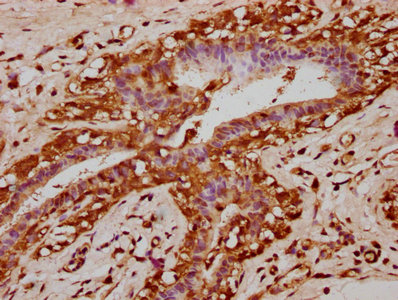

IHC image of CSB-PA769815LA01HU diluted at 1:200 and staining in paraffin-embedded human small intestine tissue performed on a Leica BondTM system. After dewaxing and hydration, antigen retrieval was mediated by high pressure in a citrate buffer (pH 6.0). Section was blocked with 10% normal goat serum 30min at RT. Then primary antibody (1% BSA) was incubated at 4°C overnight. The primary is detected by a biotinylated secondary antibody and visualized using an HRP conjugated SP system.

IHC image of CSB-PA769815LA01HU diluted at 1:200 and staining in paraffin-embedded human breast cancer performed on a Leica BondTM system. After dewaxing and hydration, antigen retrieval was mediated by high pressure in a citrate buffer (pH 6.0). Section was blocked with 10% normal goat serum 30min at RT. Then primary antibody (1% BSA) was incubated at 4°C overnight. The primary is detected by a biotinylated secondary antibody and visualized using an HRP conjugated SP system.